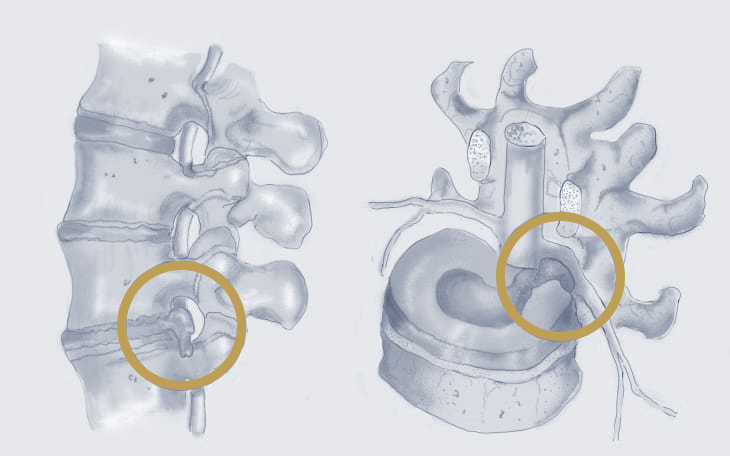

Ein Bandscheibenvorfall entsteht, wenn das weiche Innere einer Bandscheibe (Gallertkern) durch einen Riss im äußeren Faserring (Anulus fibrosus) austritt und auf umliegende Nerven oder das Rückenmark drückt.

Ein Bandscheibenvorfall tritt auf, wenn der innere, gelartige Kern der Bandscheibe (Nucleus pulposus) durch den äußeren Ring (Anulus fibrosus) hindurchtritt und auf benachbarte Nerven oder Rückenmark drückt. Bei einer Bandscheibenprotrusion wölbt sich der innere Kern (Nucleus pulposus) der Bandscheibe aus, bleibt jedoch innerhalb des äußeren Faserrings (Anulus fibrosus). Der Faserring ist dabei noch intakt.

Die Bandscheiben sind faserige, gummiartige Strukturen, die zwischen den Wirbeln der Wirbelsäule liegen. Sie bestehen aus einem äußeren Ring aus festem Bindegewebe (Anulus fibrosus) und einem inneren, gelartigen Kern (Nucleus pulposus). Ihre Aufgabe ist es, als Stoßdämpfer zu wirken, die Beweglichkeit der Wirbelsäule zu unterstützen und die Belastungen, die auf die Wirbelsäule einwirken, zu verteilen.